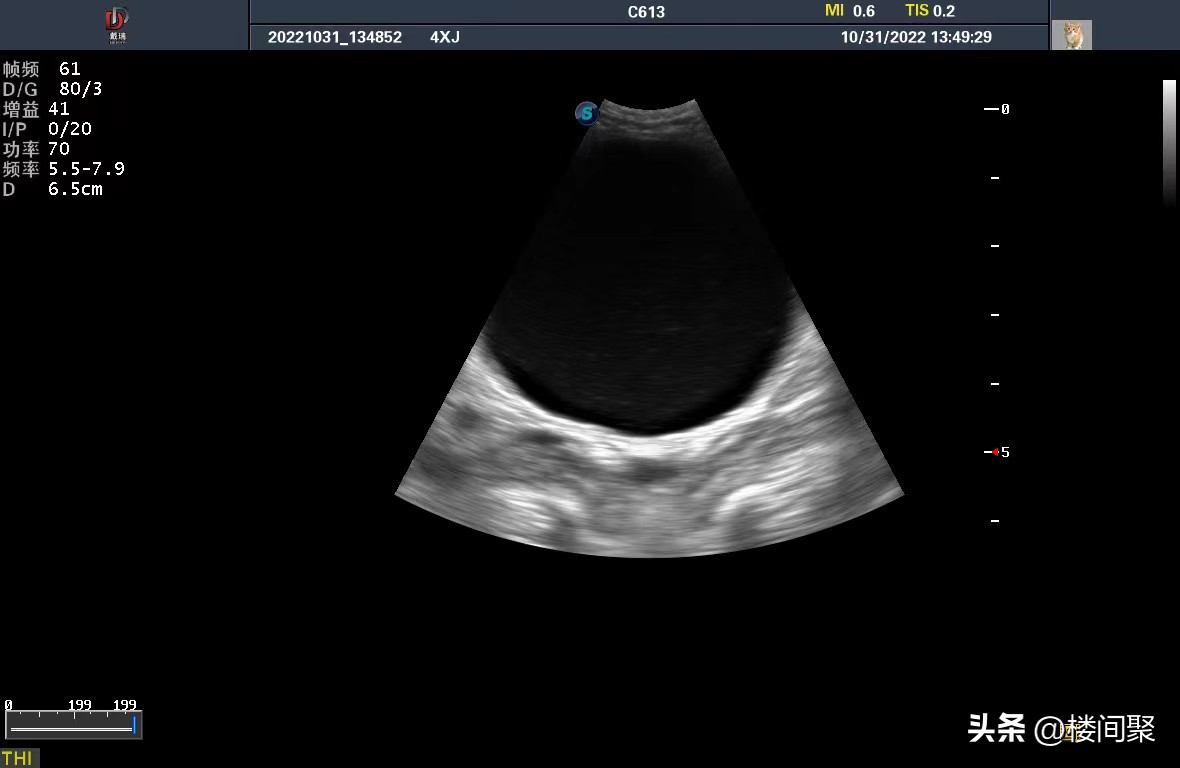

医生说不能确定是什么病,必须做检查。既然这样就做吧,医生给我列了检查清单B超、抽血、生化、CBAC+SAA四项检查一共1030元。下午结果出来,京城四小姐是公猫(我觉得我受到了刻板印象的影响,在人类的世界里女性是绝育手术的主要人群,男性掌握着生育的权利,作为一个女性我也是这么认为的,作为一个女性我觉得在潜移默化中放弃了选择权。)。

检查结果京城四小姐没有结石、是特发性膀胱炎,引起原因不明,现在需要导尿,必须住院,至少四天。一切听从医生。